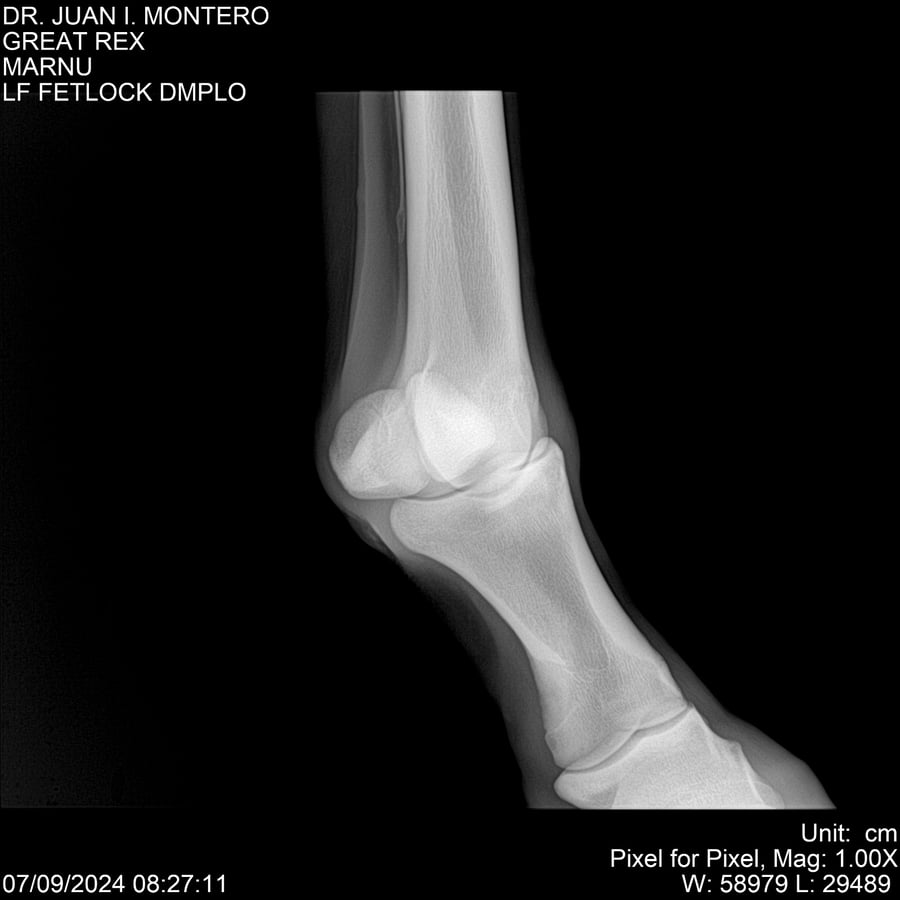

LOTE 4, GREAT REX Lote Anterior Volver al remate Lote Siguiente Ficha Contacto Montevideo - Ficha del Lote Identificador: #282518 Categoría: Yeguarizos Montevideo - 66 Visualizaciones ClicData Contacto Empresa: Abelenda N. R., Walter Hugo Nombre*: Teléfono* : E-mail* : Mensaje Enviar Registrese gratis Este contenido Exclusivo está disponible sólo para usuarios registrados Ingresar